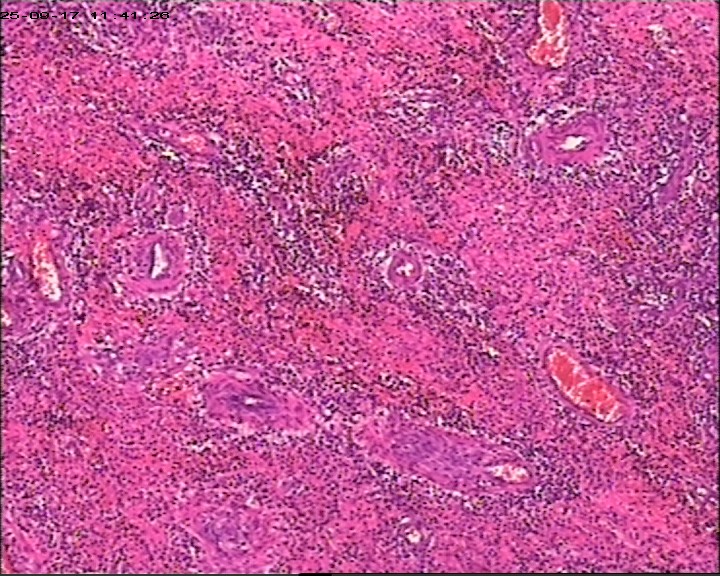

臀部组织,请帮忙看看,谢谢

性别

男

年龄

20岁

临床诊断

一般病史

藏毛窦或囊肿切开术

标本名称

臀部

大体所见

灰白灰黄碎组织一堆,大小为6.5*4*1cm。

描述诊断炎性病变